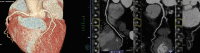

Abbildung 1: Das Bild zeigt ausgeprägte Verkalkungen (Agatston-Score > 300) im Bereich des LM, der LAD und der LCX, dies sagt aber nichts über den Stenosegrad oder über das Vorhandensein von nichtkalzifizierten Plaques aus. LM: Left Main; LAD: Left Anterior Descending Artery; LCX: Left Circumflex Artery